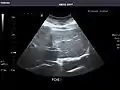

Abdominal Ultrasound (Full Exam)

STRUCTURED REPORT

(Technique: Transabdominal ultrasonography; Device: Toshiba Aplio XG)

Liver: Diffusely homogeneous and normal in echogenicity. No focal mass or contour nodularity. No intrahepatic biliary ductal dilatation.

Portal Vein: Patent main portal vein.

Gallbladder: No stones, wall thickening, or pericholecystic fluid.

Common Bile Duct: Nondilated measuring 1.3 mm at the level of the porta hepatis.

Pancreas: Visualized portions unremarkable.

Spleen: Normal in size.

Kidneys: Right and left kidneys measure 11.5 cm and 12 cm in length respectively. No hydronephrosis. Small left lower pole kidney cyst.

Ascites: None.

Aorta: Visualized portions normal in caliber, 16 x 15 mm.

IVC: Normal.

IMPRESSION:

Normal abdominal ultrasound.